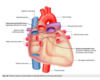

Describe the hearts shape from the anterior view

Apex of the heart hangs the most inferior and to the left, running laterally to the right is the diaphragmatic surface. The appendage (purple) is the right atrium.

Describe the shape of the heart from the posterior view

The base of the heart can be seen from the posterior view and is formed by the meft atrium NOT the diaphragmatic surface.

Below the base of the heart is the diaphragmatic surface formed by the let ventricle.

(can also see the R and L pulmonary arteries, SVC and IVC entering the Right atrium and the arch of the aorta.

The heart is a _________ structure that rotates to the _____ during development.

The heart is a midline structure that rotates to the left during development.